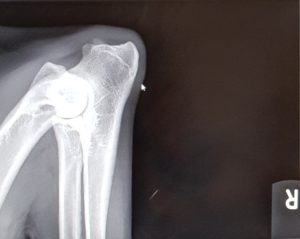

Endnu 2 hunde er blevet bedømt af DKK og fundet HD, AD og OCD frie, vi er så glade og stolte!